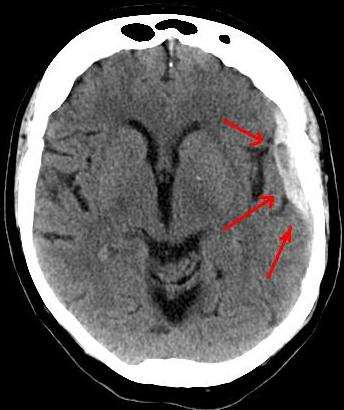

Диагнозата субдурален хематом се поставя основно чрез компютърната томография. На нея този тип хематоми имат характерна полулунна форма, представена като характерно изпъкваща зона, изпъкваща към черепната кухина. Диагнозата на субдурален хематом трябва да бъде подкрепена и допълнена също и по данни от анамнезата или на пострадалия (ако е в състояние), или на негови близки за травма на главата, по-дългия светъл период, разширената зеница, огнищната пирамидна или друга характерна симптоматика, както и постепенното изпадане в кома.

Подострият хематом обикновено е с нормални като на здравата мозъчна тъкан сенки на компютърния томограф, а хроничният субдурален хематом се представя на невроизображението като хиподензна (с други думи бледа) зона.